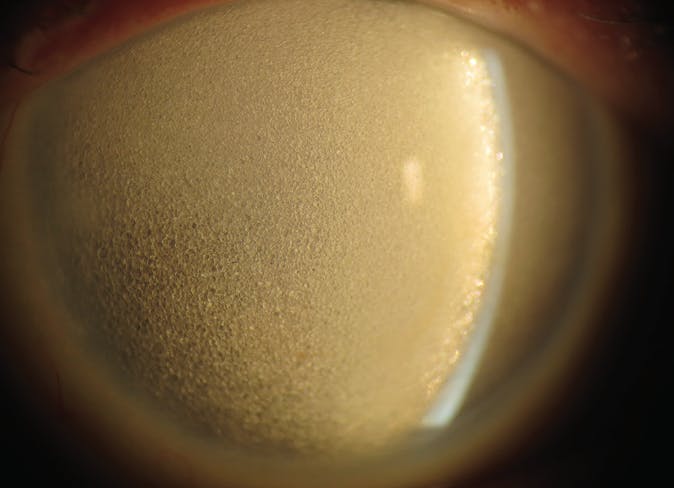

Another type of particulate glaucoma, perfluorocarbon liquid (PFCL) droplet-related glaucoma, occurs if medium-term removal of perfluoro-n-octane is inadequate after its use for inferior retinal detachment or nasal, temporal, and inferior giant retinal breaks.7,8 PFCL often becomes trapped in the zonules, residual peripheral vitreous, epiretinal membranes, and capsular bag (Figure 2).

<p>Figure 2. PFCL droplets in the inferior anterior chamber and posterior to the lens before intraoperative removal of medium-term perfluoro-n-octane.</p>

Figure 2. PFCL droplets in the inferior anterior chamber and posterior to the lens before intraoperative removal of medium-term perfluoro-n-octane.